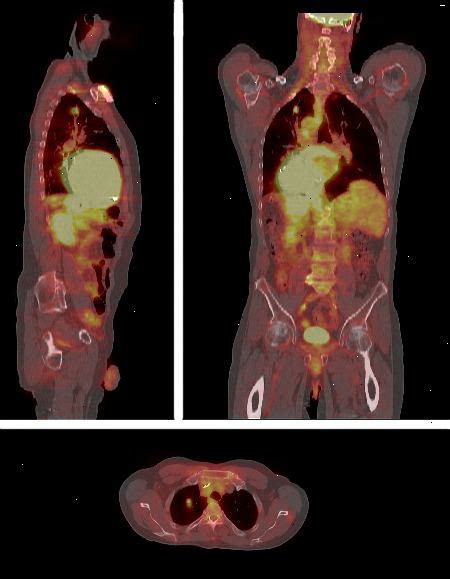

Information inför undersökning med PET-kamera. PET är en förkortning av positronemissions tomografi. Vid en PET-kameraundersökning används radioaktiva läkemedel som söker sig till ett visst organ eller viss vävnad. PET-kameran kan då registrera strålningen från läkemedlet och därigenom kan funktionen i organet undersökas. Undersökningen är smärtfri och tar i genomsnitt en timme. Eftersom du måste ligga stilla får du kuddar som stöd för huvud och kropp. Vid en PET-undersökning förs radioaktiva spårämnen in i kroppen. PET-kameraundersökning - 1177

Om PET-tekniken. Positronemissionstomografi (PET) är en bildteknik som används för att studera processer och funktion av olika organ och områden i kroppen. Genom att injicera mycket små mängder av en radioaktivt märkt biologisk substans, till exempel en aminosyra, glukos eller ett läkemedel, kan forskarna följa hur substansen fördelas. PET-scanning är vanligast används vid diagnos och bedömning av cancer. PET-tekniken lämpar sig vidare synnerligen väl för forskning på nya läkemedel. I cancermedicin, kan läkarna använda genomsökningen av följande skäl:.

Undersökning med PET- kamera används för att få veta mer om sådant som upptäckts vid en tidigare undersökning. Det kan till exempel vara att ta reda på om en tumör är cancer och om den har spridit sig. Vid undersökningen ligger du på en brits som åker in i en stor kamera. PET är en förkortning av positronemissionstomografi. Hitta rätt direkt. En PET-scan producerar tredimensionella, färgbilder av kroppen med hjälp av radionuklider för mer information om radionuklider se separat broschyr som heter Radionuklid scan.